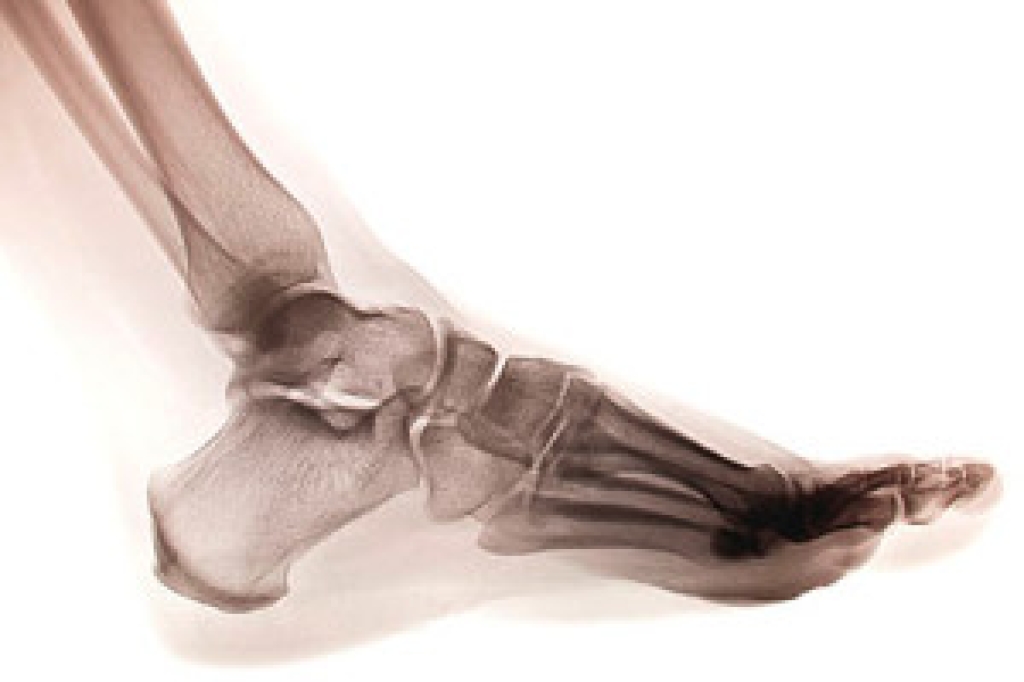

Arthritic Foot Care

Arthritis is a term that is commonly used to describe joint pain. The condition itself can occur to anyone of any age, race, or gender, and there are over 100 types of it. Nevertheless, arthritis is more commonly found in women compared to men, and it is also more prevalent in those who are overweight. The causes of arthritis vary depending on which type of arthritis you have. Osteoarthritis for example, is often caused by injury, while rheumatoid arthritis is caused by a misdirected immune system.